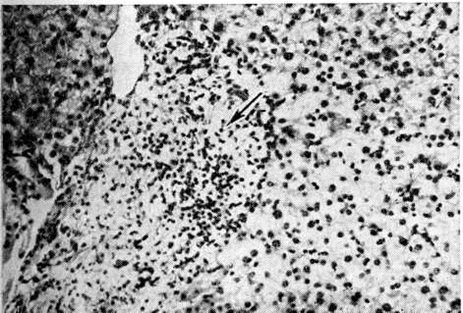

Рис. 1.

Микроскопическая картина лепроматозной гранулемы в коже: отчётливо видна свободная от инфильтрации субэпидермальная зона. Окраска гематоксилин-эозином; × 80. 1 — •эпидермис, 2 — субэпидермальная зона, 3 — инфильтрат.

Рис. 1—6.

Микроскопические картины поражений при различных формах лепры.